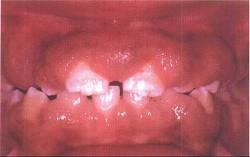

问题 药物性牙龈增生的临床表现是 ( )

选项 A.最根本的治疗是停药或换药 B.上下前牙区较重,一般不易出血 C.龈乳头可呈球状、结节状 D.只发生于有牙区 E.以上全是

答案 E